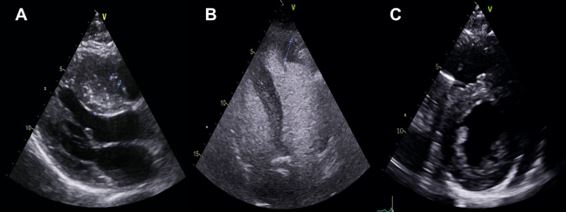

The mechanisms of MR in HCM include SAM with failure of leaflet coaptation, elongated mitral leaflets coapting in the leaflet body, anterior displacement of the mitral apparatus and PM. The anterior leaflet of the mitral valve behaves as an anterior prolapse and this arrangement in systole generates a typically mid-to-late onset eccentric lateral and posterior MR jet. Quantification of MR severity should be performed according to published recommendations and its dynamic components evaluated with provocative manoeuvres or EE3 (Figure 3).

Colour Doppler is useful to initially locate the level at which the obstruction occurs, as aliasing will occur where there is flow acceleration. To measure LV outflow tract and intraventricular gradients, continuous Doppler is used to measuring the degree of obstruction and pulsed Doppler to locate the exact point where the obstruction is occurring, since depending on the different patterns of ventricular hypertrophy, the obstruction may occur at different levels. It is therefore advisable to use pulsed Doppler from the apex to the base and outflow tract so as not to miss possible intraventricular areas of increased gradients. The typical morphological appearance of the Doppler signal is a “dagger-shaped” and late peaking curve. This is because HCM creates a vicious circle in which obstruction generates more obstruction. At the beginning of systole, ejection begins normally but as systole progresses the outflow tract narrows due to increased pressure and the pressure increases further due to the narrowing of the outflow tract thus closing the circle. Thus, the continuous Doppler contour shows a progressive flow acceleration pattern (Figure 3).